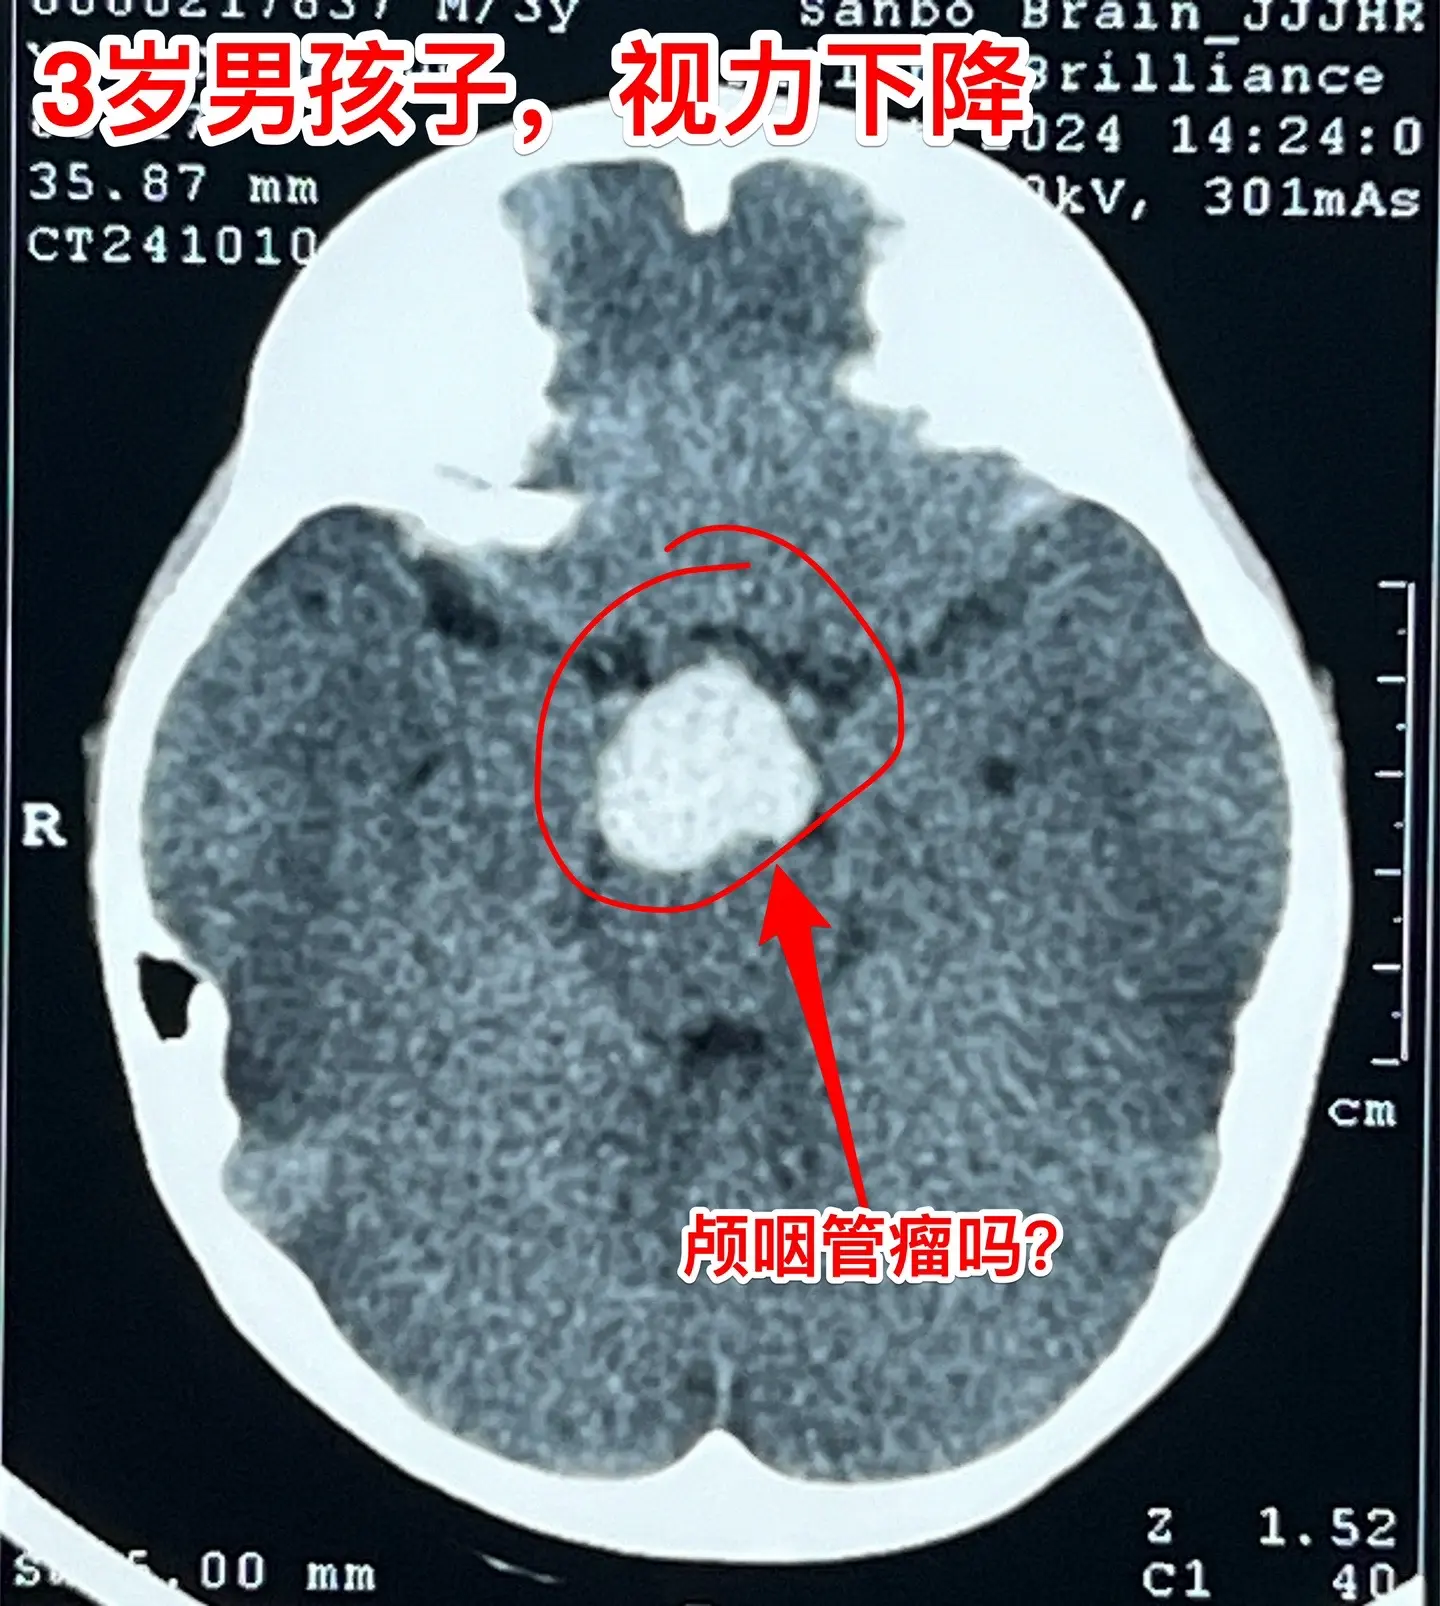

鞍区高密度囊肿-高密度不等于钙化。拉克氏囊肿在CT扫描中大多数呈低密度影,少数呈现比较均匀的高密度影,但是绝对不是钙化。不能误认为是颅咽管瘤。 三岁男孩子因偶然原因行CT扫描发现鞍区病变。测视力才发现患儿的视力有下降(0.3)。根据CT、磁共振可以判断这是拉克氏囊肿,病变没有钙化。 拉克氏囊肿如果压迫视神经、视交叉造成视力下降或者视野缺损,则有手术指征。 今日10.25经翼点入路将病变切除。术中快速冰冻报告为拉克氏囊肿。